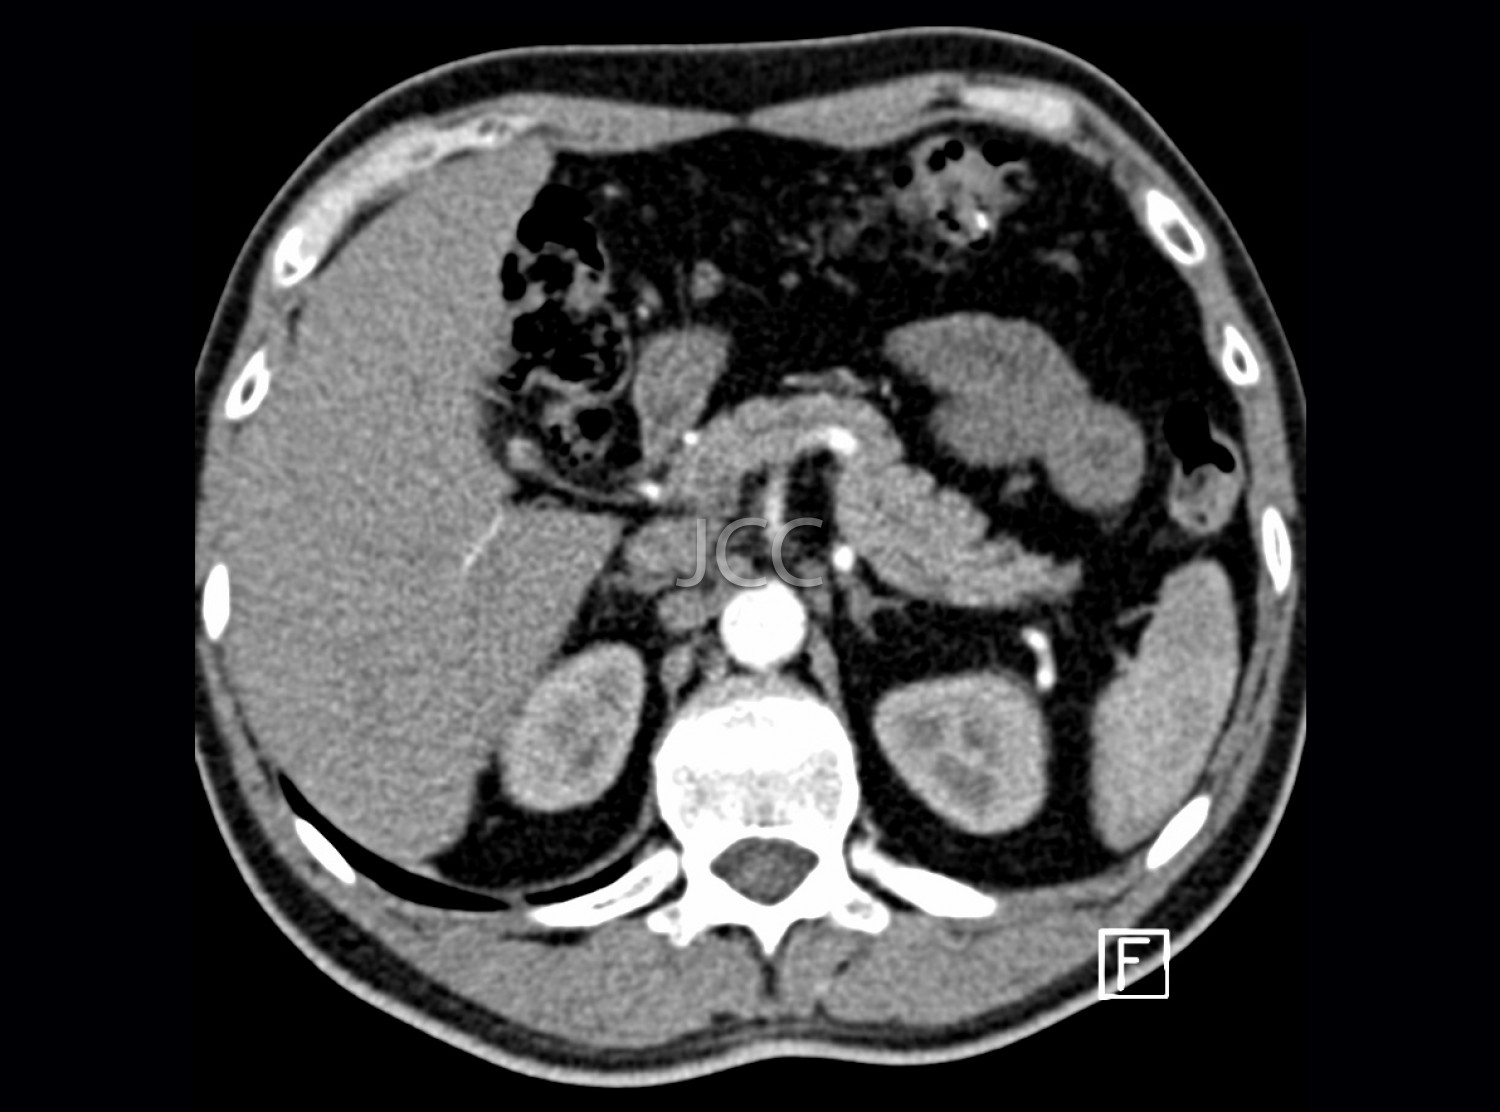

Computed Axial Tomography - Pancreatic CAT Scan

Computed Axial Tomography (CAT) - Dual Energy- 256 slices is a diagnostic technique that allows the evaluation of various parts of the human body, including the lungs, liver, pancreas, kidneys, heart, vascular structures and bone structures.